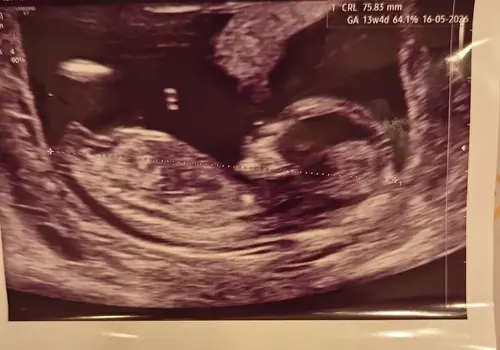

Misschien helpt dit. De echopraktijk voor pretecho’s zegt bij deze echo een meisje omdat de nub vlak loopt aan het einde.